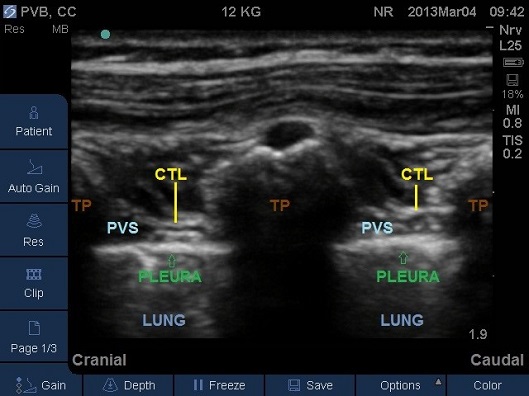

B) Probe Sagittal – Out of Plane Needle Approach

- Place an appropriate size US probe in sagittal plane over the midline. The spinous processes will be observed. Slide the probe laterally so that it is positioned parallel to the vertebral column.

- The level of the intended block should be in the middle of the probe.

- Move the probe laterally in the same plane to visualise the acoustic window between the transverse processes (Fig 17). The Paravertebral space is usually not clearly visible in this plane. Occasionally the costo-transverse ligaments can be identified. The pleura with lung beneath is clearly visible more anteriorly.

- Identify the hyperechoic round transverse process with its anechoic shadow beneath (Fig 18).

Fig 18. Parasagittal plane at mid-thoracic level. CTL – costotransverse ligament, PVS – paravertebral space, TP – transverse process.

- The needle will only be visible as a white dot; tissue plane movement or injection of a small volume of saline assists in ascertaining the position of the needle tip (Fig 19-20). Needle position is confirmed by the anterior displacement of pleura and widening of the Paravertebral space on injection.

Fig 19A and 19B. Parasagittal plane at mid-thoracic level showing initial injection of saline to assess needle tip position, note the anterior displacement of the pleura. TP – transverse process.

Fig 20A and 20B. Parasagittal plane at mid-thoracic level showing spread of local anaesthetic to adjacent paravertebral levels. TP – transverse process.